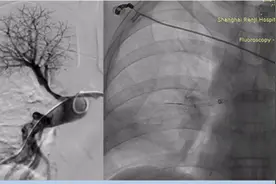

来源:【厦门日报】入院时,小张明显肿胀的左腿。(受访者 供图)春节假期刚结束,一位22岁的小伙因连续三天熬夜打游戏,突发下肢肿痛,无法下地行走,被父母紧急送到复旦中山厦门医院接受治疗。急诊检查发现,他的左下肢竟出现了一条长达半米的血栓。所幸,及时手术治疗取出血栓后,他已恢复正常。